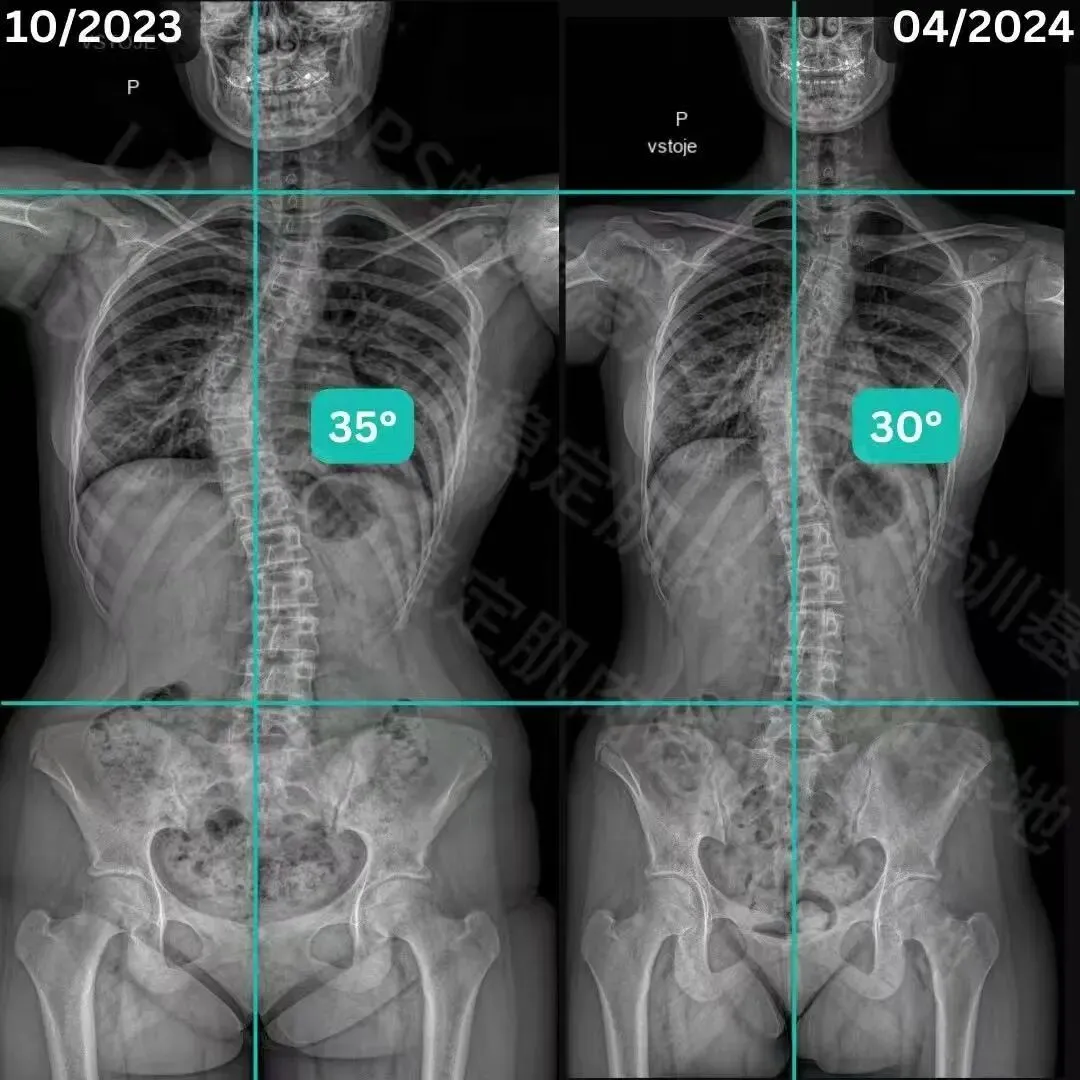

青少年侧弯改善案例

经过三个月的SPS螺旋稳定肌肉链训练

1.胸椎改善11度;2.骨盆旋转得到改善;3.体态、体轴得到改善。